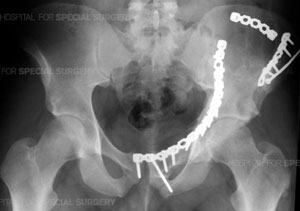

Radiograph of the pelvis following open reduction and internal fixation (ORIF) of a complex comminuted fracture of the left acetabulum, hemipelvis and pubic symphysis.

Patients with acetabular fractures often require an Open Reduction with Internal Fixation (ORIF), especially those patients who also have displacement of the joint. The surgeon realigns or reduces the bones as precisely as possible to prevent the development of post-injury related problems, especially arthritis. The bones are rigidly fixed with plates and screws to prevent future displacement and allow for rehabilitation to begin as quickly as possible.

While the Ex-Fix technique is sometimes the only procedure needed to repair a fractured pelvis, some patients require additional surgery or surgeries in which plates and screws are used internally to hold the bones in place. Depending on the site and complexity of the fracture, the surgeon may have to fix the front of the pelvis, the back of the pelvis, or both. Separate operations may be needed for each area that needs treatment.